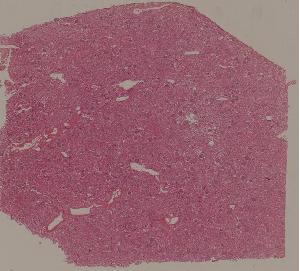

71. Acute transplant rejection of kidney